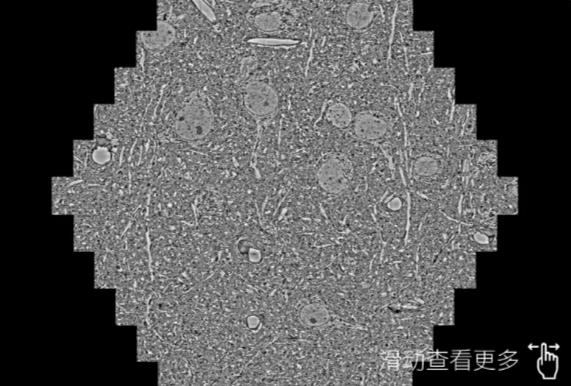

鼠脑切片。左图使用保亭蔡司保亭扫描电镜MultiSEM706对165μmx143pm面积区域成像,耗时仅需1.5秒。右图为鼠脑切片中30μm区域放大效果。样品由芝加哥大学B.Kasthuri提供。